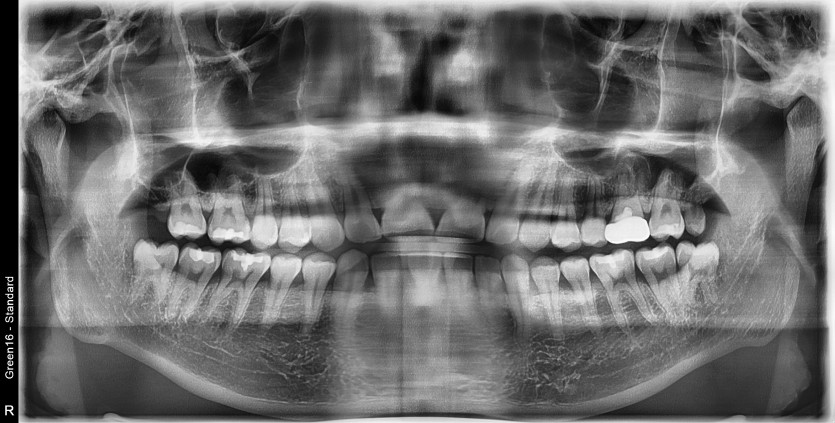

#38 사랑니 발치

구강 외과 전문의가 당일 발치했습니다.